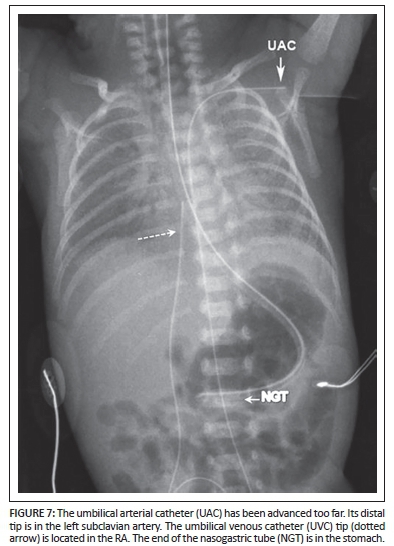

Umbilical arterial catheter (UAC)

Uses: A UAC is used in blood sampling, arterial blood gas sampling, the administration of intravenous fluids and drugs, checking blood pressure, and in exchange transfusions.

Umbilical arteries are the direct continuation of the internal iliac arteries. The UAC initially courses caudally, and then passes cranially into the aorta via the internal and common iliac arteries. It has a posterior course compared to the more anterior location of the UVC (Figure 5).

The optimum position of the UAC is either above or below the visceral branches of the aorta.3,6 It should not be in a branch of the aorta as it can block the vessel. High lines have their tips positioned between T6-10 and low lines have their tips between L3-5.3

The high position is favoured since it leads to fewer vascular complications.

Anomalous positions: Occasionally, the UAC can pass into the femoral or gluteal arteries. It can also pass into a branch of the aortic arch, for instance the common carotid artery or subclavian artery (Figure 6).

Complications

Complications include infection, thrombosis, air embolism, perforation and bleeding.3,6